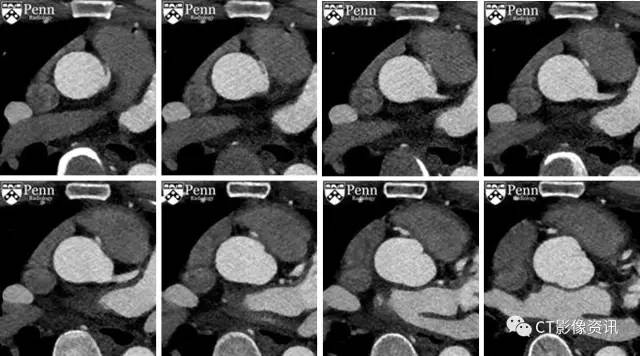

门控冠脉CTA成像,轴位图像

复习轴位图像

影像学描述 右冠状动脉从左侧冠窦异常起源,右冠与冠窦之间夹角狭窄,开口呈狭缝状改变,在主动脉根部和近端肺动脉干之间走形(或者可能恰好邻近肺动脉瓣,示例图片可能显示的不好)。右冠状动脉近端主干的管径减小。未见冠状动脉钙化。

最终诊断:右侧冠状动脉恶性的起源异常。